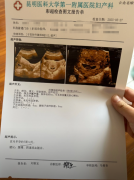

医院开的怀孕证明图片实拍(6张)

1、医院开的怀孕证明图片 2、一张医院开的怀孕证明单子 3、昆明医院开的怀孕门诊病历 4、医院开的怀孕报告单 5、昆明怀孕报告单 6、全休....